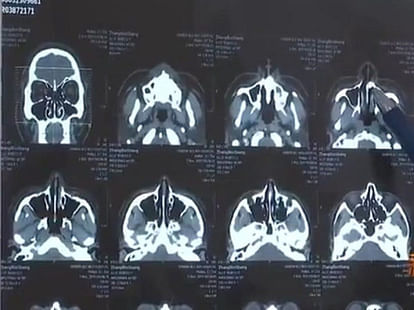

इसके साथ ही झांग को अपनी नाक से लगातार बढ़ रही गंध से भी शिकायत थी, लगातार बढ़ते जा रहे दर्द के कारण झांग बहुत परेशान रहने लगे थे। झांग ने डॉक्टर से मिलने का फैसला किया, डॉक्टरों ने उन्हें एक्स-रे कराने की सलाह दी और जब रिपोर्ट आई तो वे अपने नाक की नली के पीछे 'उच्च घनत्व' की छाया पाकर चौंक गए।

डॉक्टर ने झांग को एक ऐसी बात बताई जिसे सुनकर वो हैरान रह गए। डॉक्टरों ने बताया कि उनके मुंह की बजाय नाक में दांत उगने शुरू हो गए हैं। डॉक्टरों का ऐसा मानना है कि झांग की नाक में लंबे-चौड़े दांत उगने का कारण एक दुर्घटना है।

मीडिया में आई खबरों की मानें तो जब झांग 10 साल के थे तब वह एक मॉल की तीसरी मंजिल से गिर गए थे। इस घटना में झांग के दो दांत टूट गए थे लेकिन दुर्घटना के बाद केवल एक टूटे हुए दांत को ही खोजा गया था। डॉक्टरों के मुताबिक ऐसा लगता है कि दूसरा दांत किसी तरह जड़ से उखड़ गया और उसके नथुने में उग गया।

इस बात की जानकारी 20 सालों से ना तो झांग को थी और न ही उनके परिवारवालों को...आपकी जानकारी के लिए बता दें कि आज झांग की उम्र 30 साल हो चुकी है। हालांकि, महज 30 मिनट की सर्जरी के बाद झांग की नाक से एक सेंटीमीटर लंबे दांत को निकाला दिया गया।